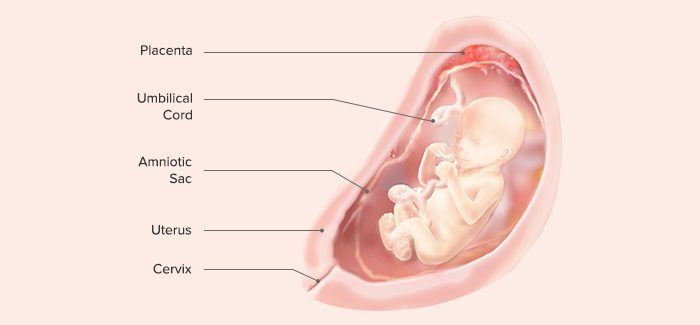

وضعیت جنین در هفته نوزدهم بارداری

حالا همه اجزا بهاندازهای که باید رشد کردهاند و پوست جنین هم با استفاده از مادهای به نام ورنیکس پوشیده شده که حالت سفید و لغزنده دارد و کمک میکند بدن جنین شما از خشکی محافظت شود. این پوشش لیزر و نرم باعث میشود کودک شما در هنگام زایمان در مجرای زایمان راحتتر حرکت کند.

مایع مغزی نخاعی که در اطراف نخاع و مغز قرار گرفته در شبکه عروقی مغز تشکیل شده است و جوانههای دندانهای دائمی نیز پشت دندانهای شیری رشد کردند و جنین خیلی راحت مایع آمنیوتیک را مینوشد.

از هفته نوزدهم بارداری رودههای جنینتان هم کار خود را آغاز میکنند و با ترشح کردن شیره روده جذب مایع آمنیوتیک بالاتر میرود و کلیهها این مایع را تصفیه میکنند و کودک دیگر میتواند درون آب آمنیون ادرار کند و نیازی به نگرانی از این بابت نیست چون هر چند ساعت یکبار این مایع تصفیه میشود.

بیشترین اضافهوزنی که در بدن مادر در هفته نوزدهم رخ میدهد اطراف شکم و باسن است که حدود 3 تا 6 کیلوگرم است و وزن جفت در این زمان حدود 170 گرم هست و مایع آمنیوتیک و رحم حدود 350 گرم بهصورت مجزا وزن دارند.